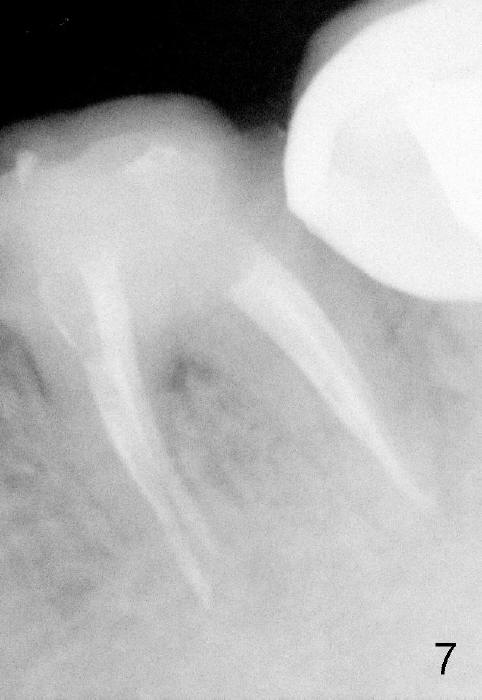

近中根管扩大麻烦,只能慢慢来,逐渐失去working length,X光片证实(图五:MB:30/.06主牙胶尖; ML:十号扩大针),之后继续努力,向根尖进军。近中舌侧根管主要使用hand files,直到三十号,尽量往侧壁拉,让断针松弛,最后利索通过rotary file 30/.06一次,充填前再拍摄一张根尖片,希望无意中断针被冲洗出来(病人期待能把断针取出,她胆小,好不容易下定决心重做根管治疗),结果白日做梦,断针还在原处(图六),偶尔能取出自己造成断针,这次却不行,反正丑媳妇不怕见公婆,在二点五倍loops下,断针始终看不见。最后完成根管充填(四个根管都用30/.06主牙胶尖)和buildup(图七),充填好像不尽人意,这时精疲力竭,好在病人还感激,接着制作临时牙冠,打发病号。术后一两天病人还有些疼痛,只好观察,后来把她忘却。今天术后两周她突然回诊所,昨天把临时牙冠咬断(图八),我们重做临时牙冠,用永久性粘固粉,她准备明年做两个牙冠,想充分使用牙科保险钱。最振奋人心的是她张口痛完全消失,看样子术前没有TMD,虚惊一场。